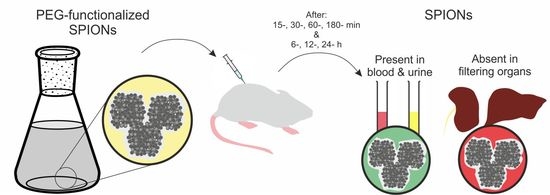

2.1. SPION-PEG Clusters Synthesis and Characterisation

2.2. In Vivo Distribution and Clearance Analyses

2.2.1. Animal Model and SPION-PEG Clusters Administration

3.1. SPION-PEG Clusters Characteristics

3.2. SPION-PEG Cluster Distribution and Clearance